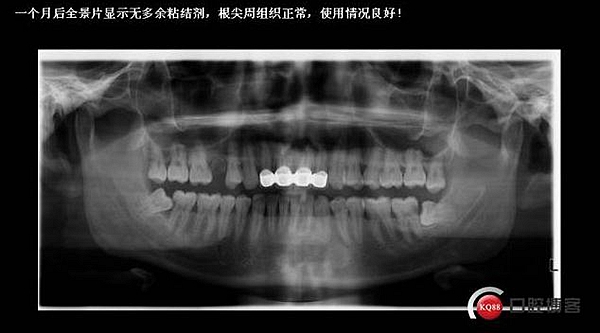

口內(nèi)檢查:很輕易就取下牙冠,均為殘冠殘根且繼發(fā)齲,#21尤為嚴重,已到齦下,牙周探診1.5mm,X線檢查:根尖陰影,欠充。